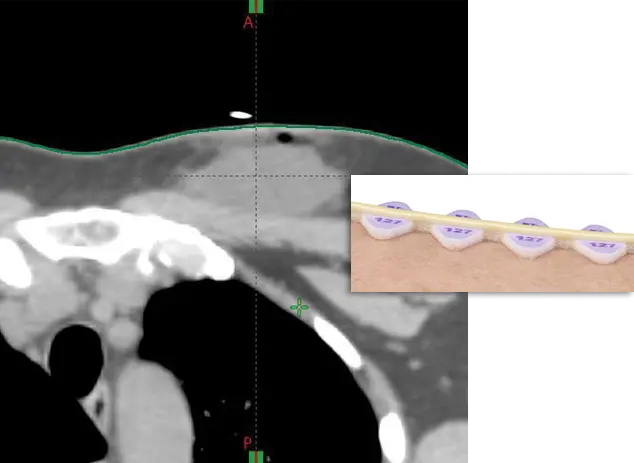

The only skin markers for CT simulation elevated from the skin line to help exclude marker from the automatic body contour.

The only skin marker for CT simulation that is elevated from the skin line and helps to exclude the marker from the automatic body contour

RT-SPOT is an elevated skin marker designed to minimize dose perturbation and reduce the need for manual contouring.

RT-SPOT® Line is flexible, contours easily into desired shapes, and stays in place without lifting. Ideal for marking field borders, tangents, scars, sarcomas, and larger treatment areas.